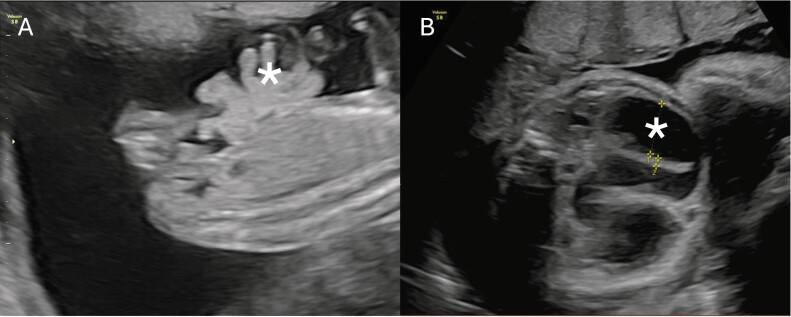

A newborn of 32 + 6 weeks' gestational age with prenatal diagnosis of gastroschisis was born through elective caesarean section. Ultrasonography at 16 + 4 gestational weeks (GW) showed a gastroschisis with free bowel loops floating in amniotic fluid. From 27 + 4 GW onward, serial ultrasounds showed the disappearance of extra-abdominal intestine and progressive intra-abdominal intestinal loops dilation, raising suspicion for vanishing gastroschisis. Birth weight was 2,136 grams and the external appearance of the abdomen was normal. An exploratory laparotomy was performed, finding a dilated proximal jejunal loop with a type III intestinal atresia, microcolon, and no other remainder bowel in between. The total length of the small intestine was 21 cm. Serial transverse enteroplasties for intestinal lengthening (reaching 38 cm), along with lateroterminal jejunocolic anastomosis were performed. The patient was discharged after 5 months of hospitalization with home parenteral nutrition. At 2 years and 8 months of age, the child is thriving and off parenteral support. Vanishing gastroschisis is a rare and severe form of complex gastroschisis whose prenatal diagnosis is crucial for parental counseling, timely delivery, and early surgical intervention. Multidisciplinary approach is essential to manage intestinal failure and improve long-term outcomes in these patients.

本文报道一胎龄32 + 6周,产前诊断为胃裂的新生儿通过选择性剖宫产出生。孕16 + 4周(GW)超声检查显示胃裂,游离肠袢漂浮在羊水中。从27 + 4gw开始,连续超声显示腹外肠消失,腹内肠袢进行性扩张,怀疑胃裂消失。出生体重2136克,腹部外观正常。进行剖腹探查,发现空肠近端袢扩张伴III型肠闭锁、微结肠,其间无其他剩余肠。小肠总长度为21 cm。连续行横向肠成形术延长肠长度(达38厘米),同时行侧端空肠结肠吻合。患者住院5个月后经家庭肠外营养治疗出院。在2岁零8个月大的时候,孩子正在茁壮成长,不需要外部支持。消失性胃裂是一种罕见且严重的复杂胃裂,其产前诊断对家长咨询、及时分娩和早期手术干预至关重要。多学科方法对于治疗肠衰竭和改善这些患者的长期预后至关重要。